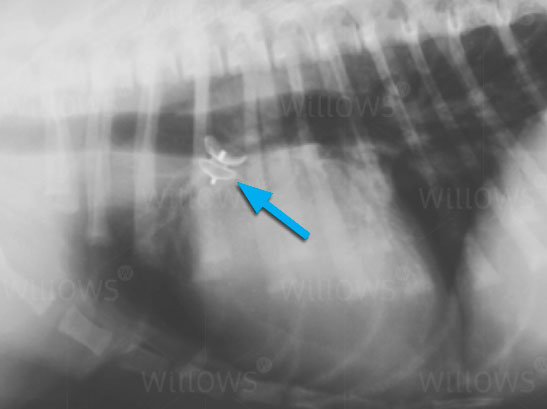

Fig 2:

Once the first test has confirmed the ACDO (arrowed) is in a good position, it is then released from the delivery catheter.